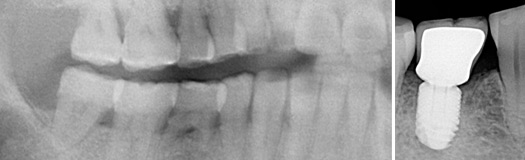

Une molaire du bas perdue serra remplacée par un implant.

Une molaire du haut perdue remplacée par une racine artificielle.